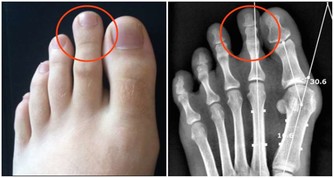

一、血管發生堵塞,腳會出現3個異常,若佔一個,提醒你要注意了

*****3、異常三:腳腫*****

血管堵塞,血液的流通受阻,進而就會造成腳經常水腫。